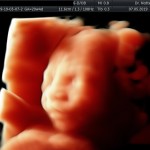

Modalidad de imagen ecográfica que permite evaluar, medir y capturar estructuras fetales superficiales e internas en 3 dimensiones (3D) y también en movimiento y en tiempo real (4D) con programas de realismo aumentado (HD LIVE) e imágenes tomografías fetales (TUI) mejorando significativamente la precisión en las mediciones fetales y la documentaciones de estructuras anatómicas.

Esta tecnología se puede utilizar desde la 6ta a la 40ma semana de embarazo.